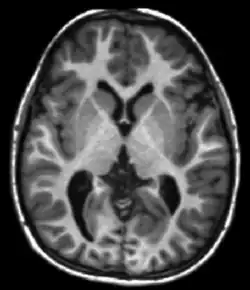

Neuroimaging

MRI is the investigative tool of choice for neurological cancers over CT, as it offers better visualization of the posterior cranial fossa, containing the brainstem and the cerebellum. The contrast provided between grey and white matter makes MRI the best choice for many conditions of the central nervous system, including demyelinating diseases, dementia, cerebrovascular disease, infectious diseases, Alzheimer's disease and epilepsy.[22][23][24] Since many images are taken milliseconds apart, it shows how the brain responds to different stimuli, enabling researchers to study both the functional and structural brain abnormalities in psychological disorders.[25] MRI also is used in guided stereotactic surgery and radiosurgery for treatment of intracranial tumors, arteriovenous malformations, and other surgically treatable conditions using a device known as the N-localizer.[26][27][28] New Artificial intelligence in healthcare tools have demonstrated higher image quality and morphometric analysis in neuroimaging with the application of a denoising system.[29]